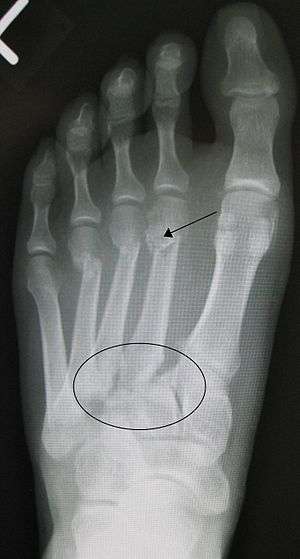

| Lisfranc fracture (marked by the oval) with fractures of the distal second (marked by the arrow), third, and fourth metatarsal bones | |